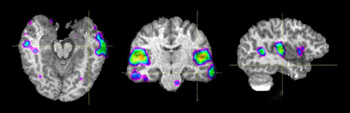

Las vistas ortogonales hacen referencia a un conjunto de imágenes mutuamente perpendiculares. Esto localiza una región determinada de activación en los tres ejes que definen la forma volumétrica del cerebro.

Voluntario adulto que genera verbos. En la vista axial, la ubicación exacta de la activación en el lóbulo temporal es difícil de determinar. Las líneas negras en la vista axial corresponden a la ubicación de las vistas sagital y coronal. Estas tres vistas nos permiten determinar la ubicación de la activación en la circunvolución temporal media.

Paciente adulto de sexo masculino diestro con convulsiones intratables provenientes del polo temporal izquierdo y que realiza una tarea de lenguaje que consiste en escuchar una historia. No se detectaron lesiones estructurales en esta región. Está programada una resección temporal izquierda. Las vistas ortogonales permiten evaluar la extensión de las áreas del lenguaje y la distancia entre su borde anterior y el polo temporal (línea de color anaranjado). El neurocirujano puede usar estos hallazgos como guía para adaptar la resección temporal.